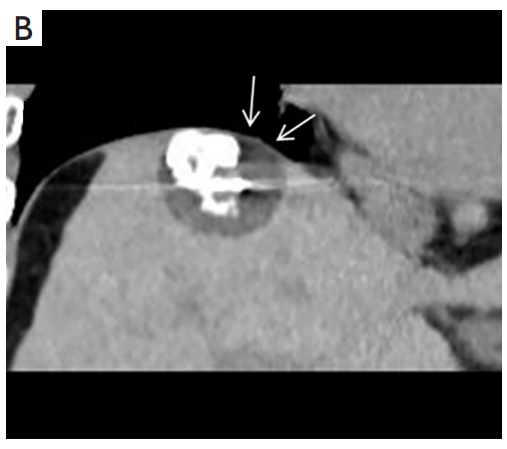

③ 高危部位术中消融情况:冠状面CT图像经多平面重建冷冻消融时,肿瘤完全被冰球(箭头)覆盖。